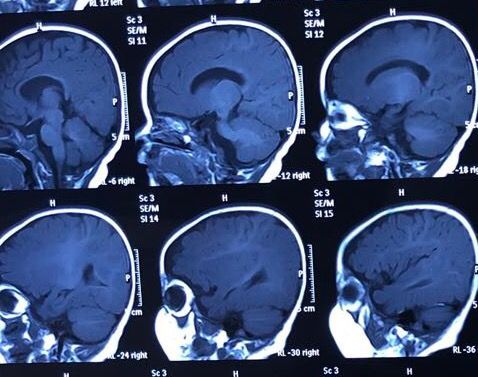

生后3月复查头颅核磁共振

生后3月复查头颅核磁共振